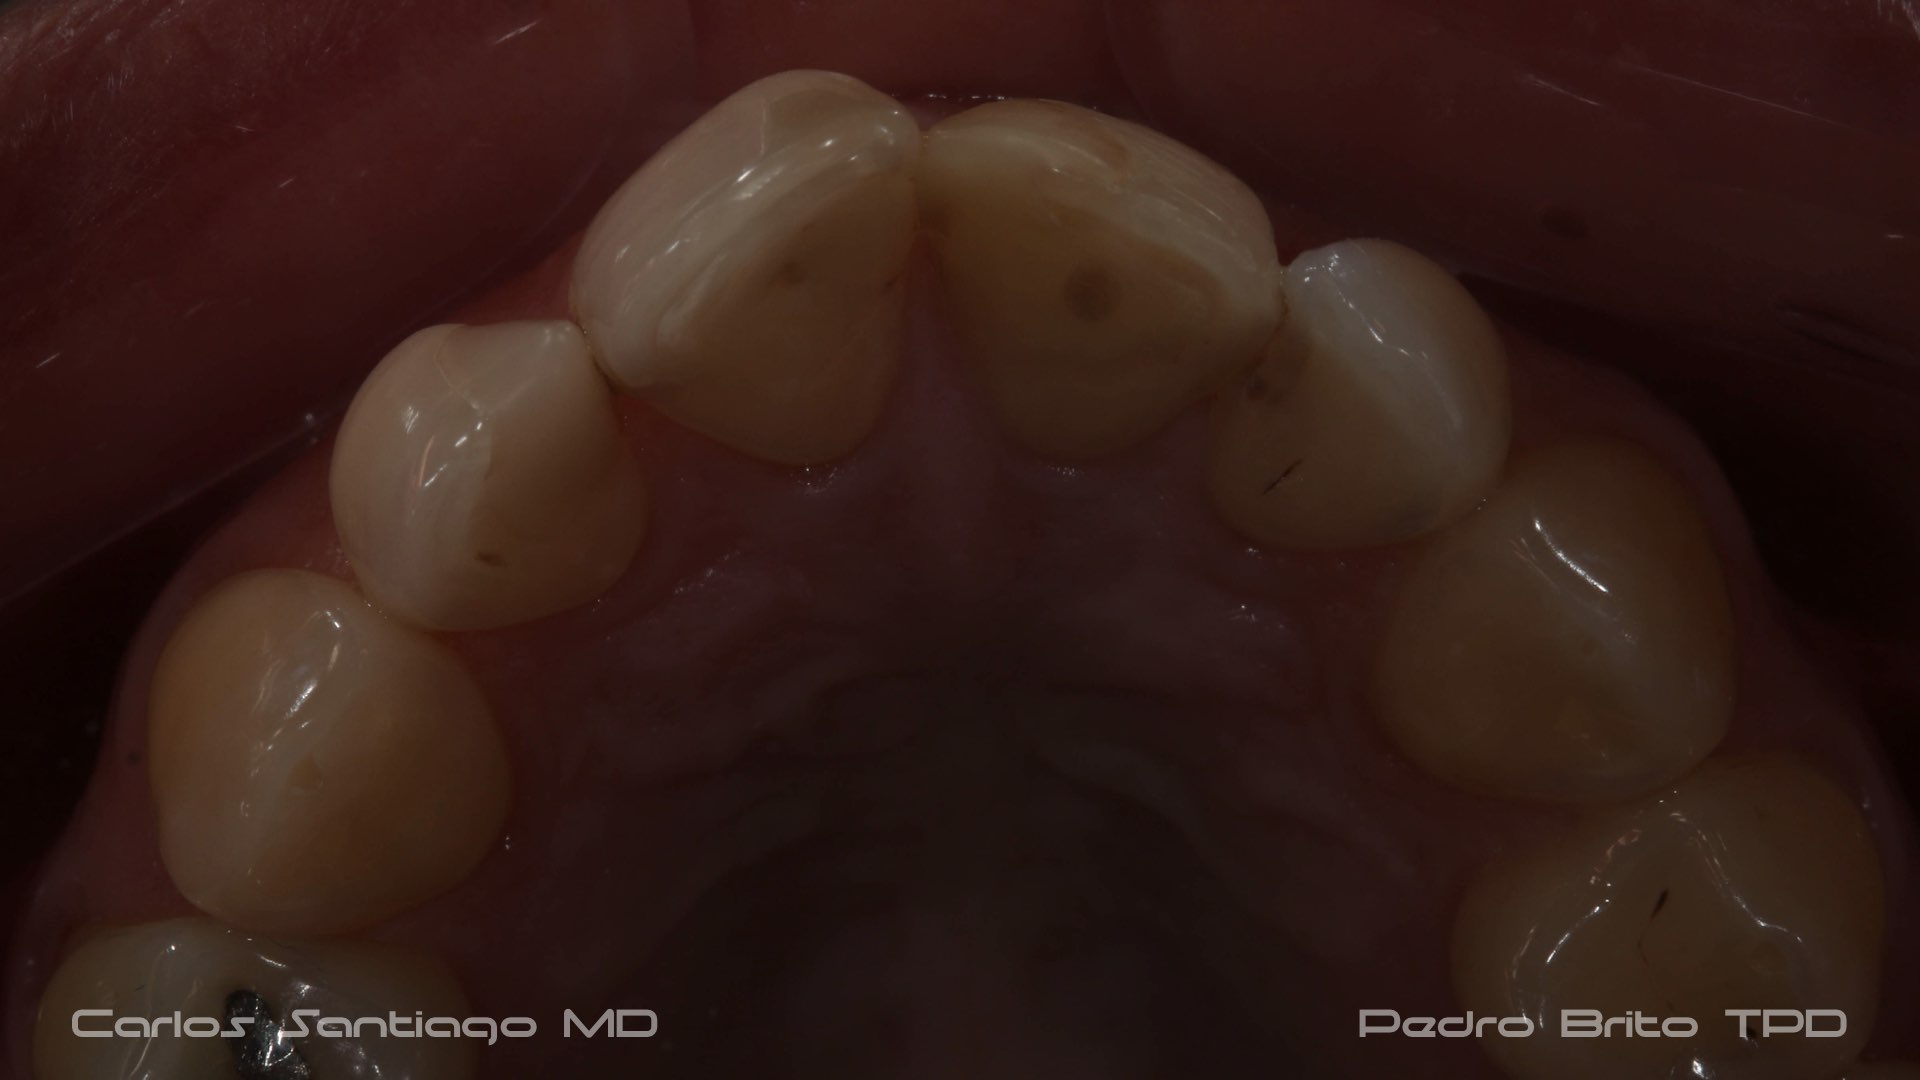

As Facetas Cerâmicas (lentes de contacto dentárias ou laminados), permitem corrigir da maneira mais estética e conservadora possível, problemas de forma e tamanho, côr e posição dos dentes, bem como substituir restaurações antigas e inestéticas.

São aderidas químicamente ao esmalte dentário de uma forma permanente, com o objectivo de melhorar a estética dos nossos pacientes.